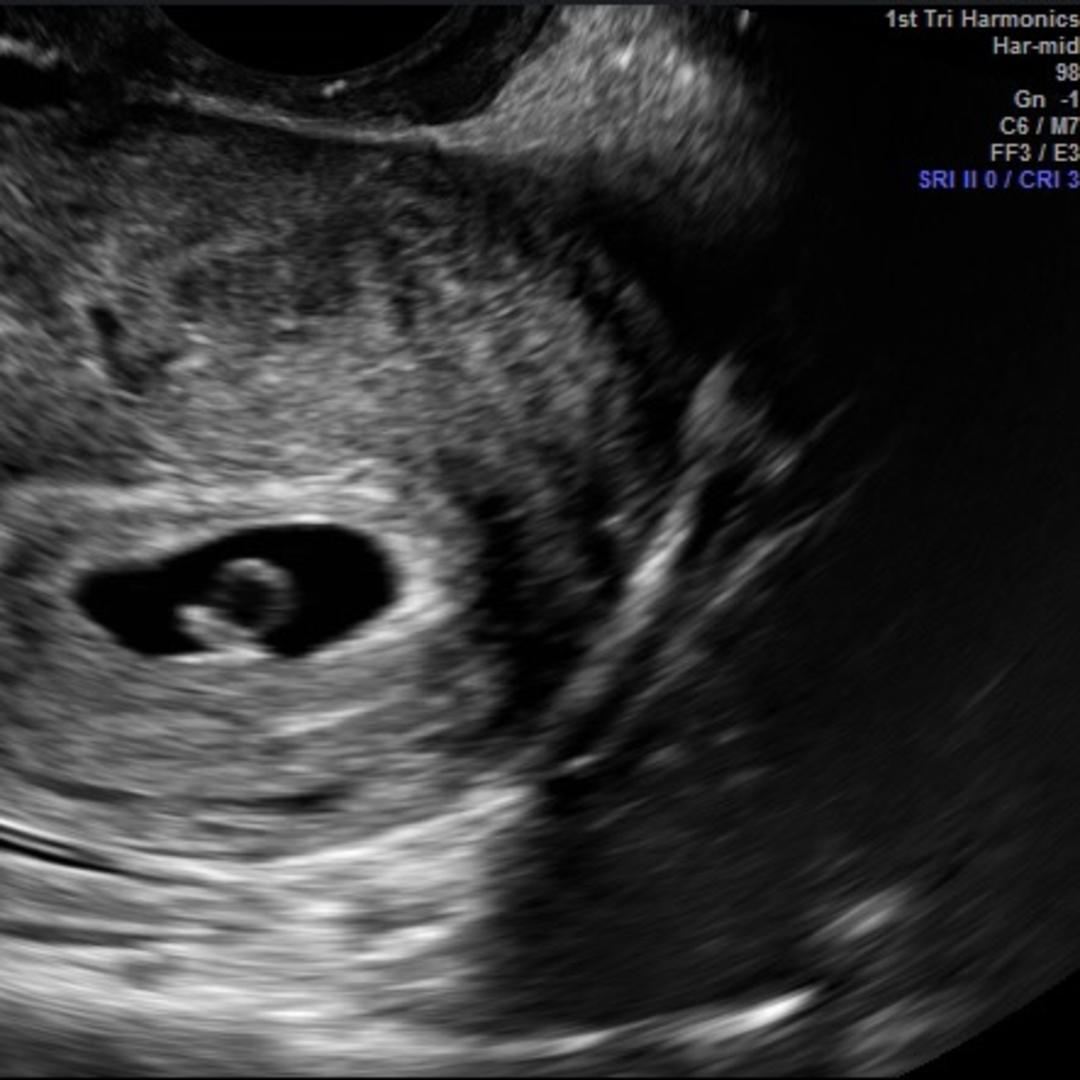

Hello family and friends! We are absolutely thrilled to have you all join us in celebrating our baby girl Isabella! It warms our hearts to know she is so loved and anticipated by her village. See you all in Florida in May and/or Baltimore in June!